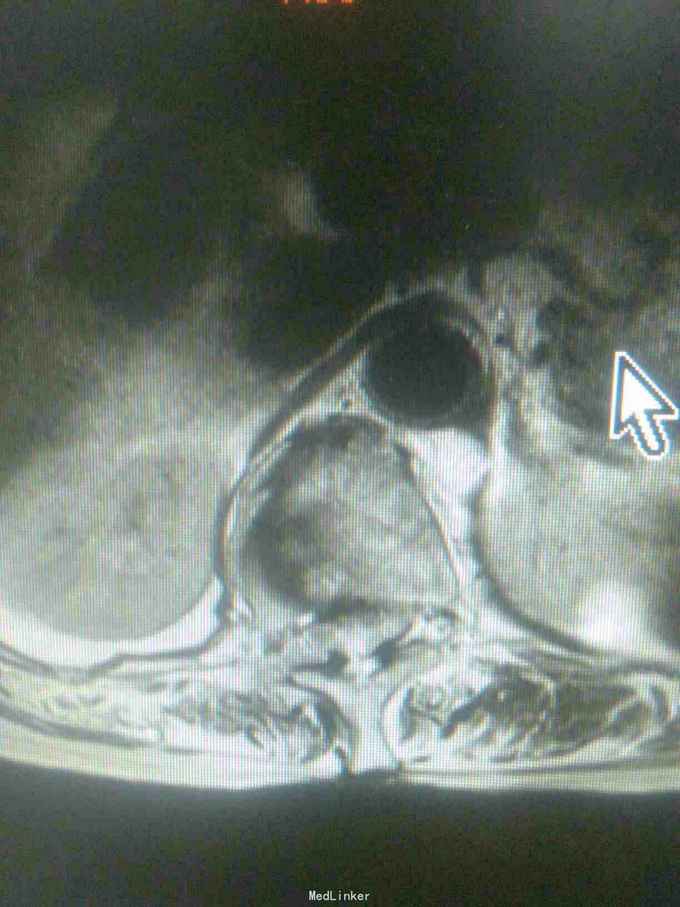

患者女,71岁,因双下肢无力,活动障碍5年余,不能行走半年。患者自诉于5年前无明显原因及诱因下逐渐出现双下肢无力,开始以双足部、双小腿为主,后整个下肢都感到无力,到入院半年前不能站立行走。大小便功能正常。

查体,双下肢肌肉萎缩,肌张力高,双侧大腿肌力3级,双小腿肌力2级,双足部肌力0级,双足部疼觉减退,会阴及双大腿、小腿感觉均正常,腱反射未引出,肛门反射、腹壁反射可引出,肛门括约肌未见松驰,双上肢查体正常。

目前诊断:双下肢瘫痪查因。

请教各位同行老师,这个考虑是什么问题,需要进一步完善什么检查。